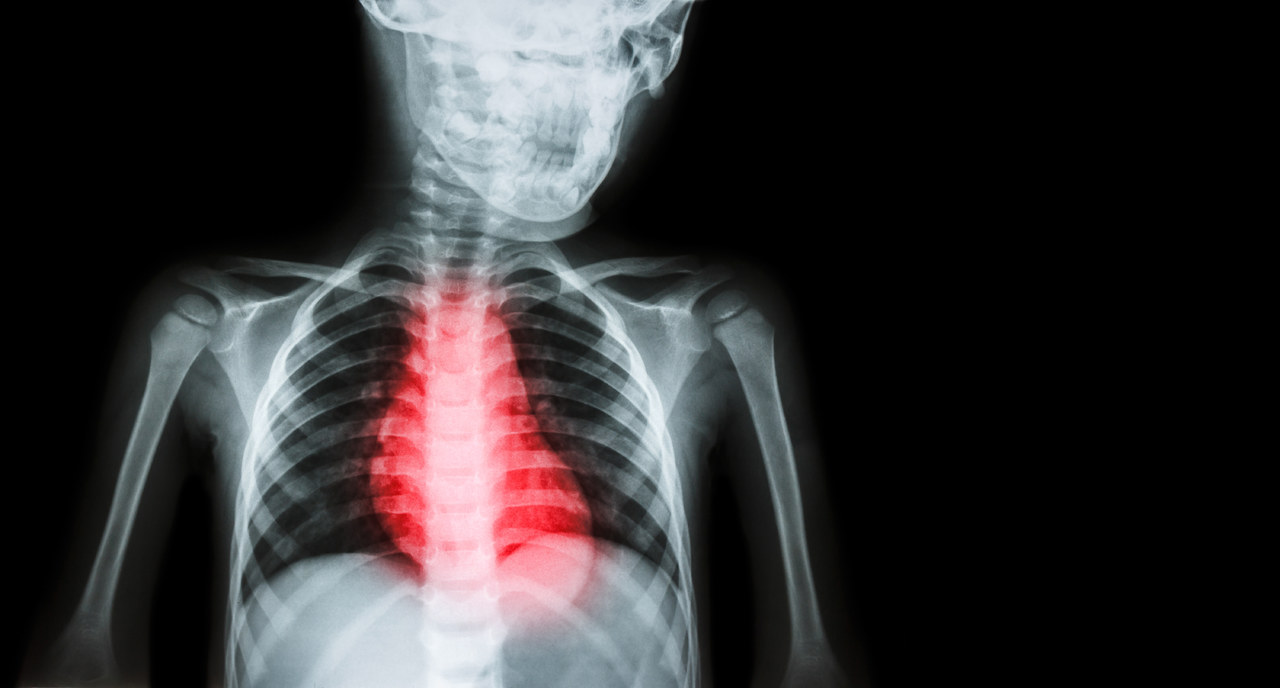

心脏|心脏支架缺德害人,装了人就活不长?实话说支撑生命的是4点认知

?一、 为何做完心脏支架 , 还会猝死?

首先 , 我们要明确一个观念 , 心脏支架是一种治疗手段 , 并不能让疾病一劳永逸 。

心脏支架手术能够解决当前狭窄部位的血管问题 , 然而其他较远部位的血管 , 仍然可能会出现狭窄的情况 , 甚至血管完全堵塞 , 而导致功能丧失 。 这时候就算疏通了大血管 , 也很难支撑心脏正常功能 , 患者就容易因为其他血管堵塞而发生猝死 。 换句话说 , 人体血管有很多根 , 你的A血管堵塞了 , 发生了堵塞 , 这个时候植入心脏支架 , 只是解决了你A血管的堵塞问题 , 并不能保证除A血管以外 , 其他血管的堵塞问题 。

此外 , 支架的目的是为了疏通堵塞的血管 , 但是在这个过程中也可能会产生新的问题 , 比如容易压迫周边的小血管 , 或者导致原有的斑块进入周边的小血管 , 最终导致这些血管堵塞而引发危险 。

因此 , 心脏支架手术只是针对血管的狭窄之地进行 , 并不能保证其他的血管不狭窄 , 所以仍然有猝死的可能 。